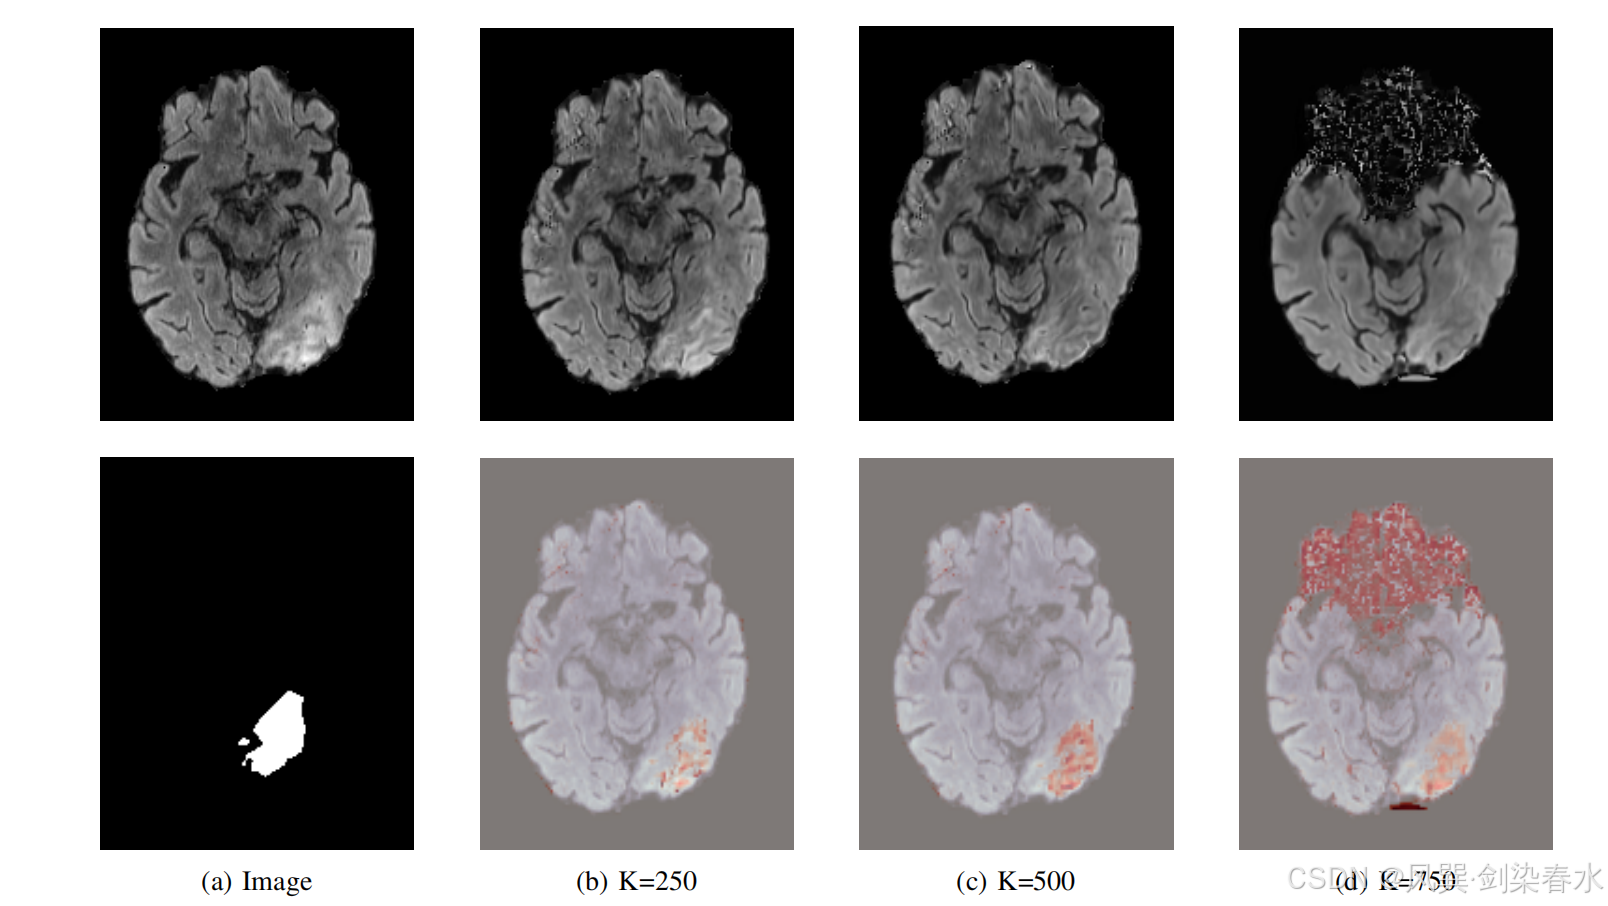

Figure 5 | 在验证数据集上,使用不同的阈值百分位数来二值化显著性图以及不同的噪声量 K K K 所获得的 Dice 分数: 在 K = 500 K=500 K=500 以及使用显著性图中第 90 百分位的像素时,能够获得最佳结果;

Figure 7 | 来自 BraTS 2021 的原始图像及其真实的分割掩码(a),以及通过 Dif-fuse 生成的健康图像(顶部行)和对应的异常图(底部行),其中分别使用了 250(b)、500(c)和 750(d)步的加噪过程: 当使用较低的噪声量时,病理区域未能被完全移除;而当噪声水平过高时,则可能会引入显著的伪影;